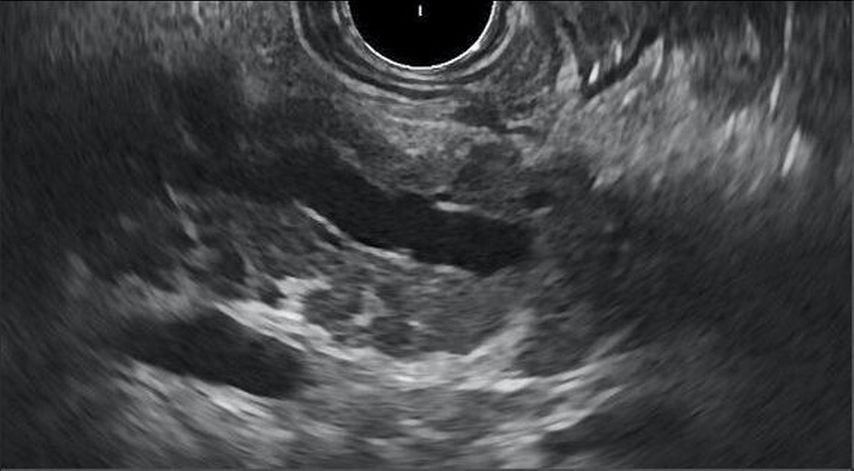

Fig.1: Image d’endo-échographie d’une pancréatite chronique. Nos données montrent que la pancréatite chronique est plus fréquente chez les personnes vivant avec le VIH que dans la population séronégative pour le VIH. Elle est présente chez 21% des personnes examinées, alors que la prévalence chez les personnes séronégatives pour le VIH est de 1‰ maximum selon la littérature (Göbbert A. 2023).10

Ce résultat cliniquement pertinent corrobore la thèse selon laquelle le spectre de la maladie va souvent bien au-delà du statut de séropositivité pour le VIH. Les comorbidités qui s’ajoutent à la maladie sous-jacente exigent une attention particulière, des efforts diagnostiques et une gestion cohérente. Cela peut uniquement réussir à l’aide d’une prise en charge coordonnée ou dirigée activement. L’infectiologie joue un rôle central